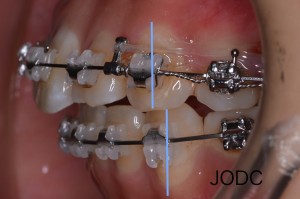

【2】カリエール

上顎前突「出っ歯」の改善を目的とする装置で、上顎左右犬歯から大臼歯を遠心移動する為に使用します。

“カリエール”を口腔内に装着し、下顎左右第一大臼歯の装置とカリエールに顎間ゴムをかけます。

顎間ゴムをかけることで上顎は後方へ、下顎は前方へ誘導される力がかかります。この作用で上下顎の顎関係の改善をはかります(After写真は約1ヶ月後)。

犬歯から第一大臼歯にかけて遠心移動し、上下顎がしっかり咬み合う所まで誘導できました。カリエールを装着する事で後の矯正治療で行うブラケット装置での治療期間を短縮することができます。